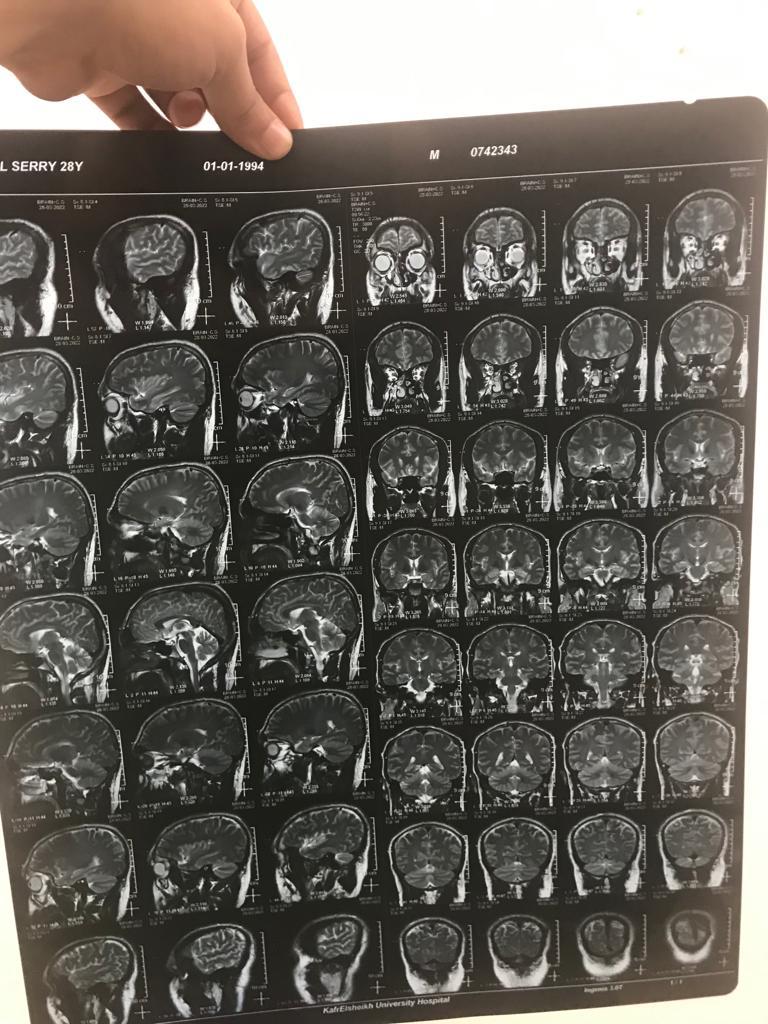

بعد استشارة عدة أطباء، اكتشف أمجد أن السبب هو إصابته بالتصلب الضموري الجانبي، والذي نتج عنه ضمور بالأطراف الأربعة، حيث يتزايد بصورة سريعة منذرا بشلل رباعي.

يروي الدكتور أمجد، ابن محافظة كفر الشيخ لـ القاهرة 24 تفاصيل مرضه: تعبت من شهر يناير اللي فات، ولما كشفت طلع عندي التصلب الضموري، وأخذت العلاج اللي في مصر، مجبش نتيجة.

يقول الطبيب: العلاج بيوقف تطور المرض مش بيعالجه بشكل كامل، وسعر القرص الواحد لمدة 3 أشهر يتراوح بين 30 إلى 35 ألف جنيه، ونفسي صوتي يوصل للمسئولين.